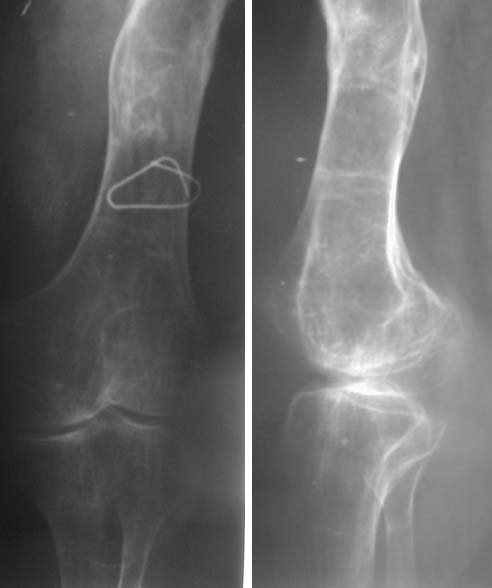

Судя по представленному снимку, есть 3 деформации – Варусная в области ложного сустава - 70°, Вальгусная - 35° в средней трети бедра, и ещё одна вальгусная 8° в области дистального метаэпифиза бедренной кости. Если бы пациент попал ко мне, я сделал бы трилокальный остеосинтез – Открытый погружной копрессионный в области ложного сустава, остеотоми на вершине деформации средней трети бедра для удлинения и коррекции деформации и коррегирующую остеотомию через верхний край мыщелков бедренной кости. Для оппонентов такой тактики сразу оговорюсь, что коррекция анатомической и механической оси при наличии срастающегося ложного сустава критична для профилактики рефрактуры.

Кольцо на средний фрагмент, с 2-мя спицами 2-3 полустержнями типа Шанца. 2 кольца на дистальный фрагмент на спицах. В случае второй остеотомии – колцо в области мыщелков с 2-мя спицами и 2-мя полустержнями типа Шанца, проведёнными в плоскости кольца по одному в каждый мыщелок с зади к переди в соответствии со строением каждого мыщелка.